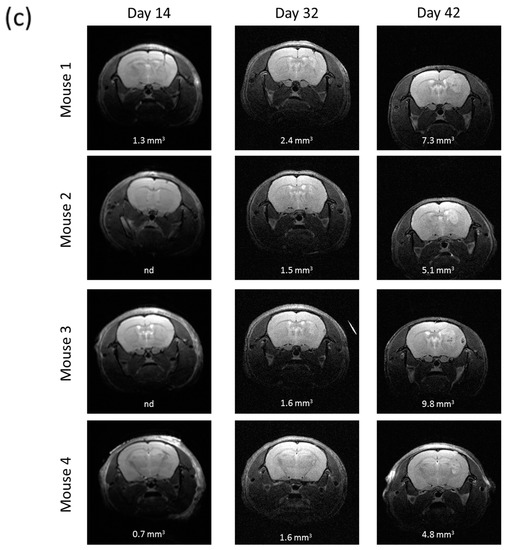

All the nude mice intracranially implanted with R2J cells cultivated in monolayer (2 × 105 cells, n = 4) and in spheres (2 × 105 cells, n = 4 and 1000 cells, n = 4) were tumor bearing (Figure 4). Two weeks after the implantations, MRI revealed the presence of tumors in mice, which was confirmed 56 days post implantation (PI) for monolayer cells (Figure 4a) and 32 days PI for spheres (Figure 4b,c).

Figure 4.

In vivo tumorigenicity of R2J cells after intracranial implantation in nude mice of (a) 2 × 105 cells cultivated in the monolayer (b) 2 × 105 or (c) 1000 cells cultivated in spheres. MRI acquisitions were performed post implantation at the times indicated. Mice were sacrificed after the last MRI. Tumor volumes were calculated by adding each tumor x slice thickness (0.5 mm²). (a) Implantation of 2 × 105 R2J monolayer cultivated cells. (b) Implantation of 2 × 105 R2J sphere cells. (c) Implantation of 1000 R2J sphere cells.

The xenograft of R2J cells cultivated in 2D or in spheres resulted in the formation of a detectable tumor within 14 days post implantation into the striatum of nude mice. These results allowed conclusions on the tumorigenicity of this cell line and on its CSC properties [7]. Indeed, only 1000 spheres isolated from the total R2J-2D population were able to trigger a highly proliferative tumor growth.